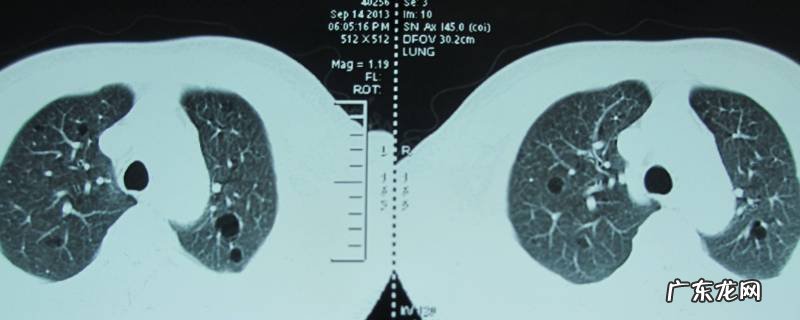

【气之主指的是什么,气之主指的是哪个脏器】肺 。肺是人体的呼吸器官 , 也是人体重要的造血器官 , 位于胸腔 , 左右各一 , 覆盖于心之上 , 被称为气之主 。肺有分叶 , 左二右三 , 共五叶 。肺经肺系(指气管、支气管等)与喉、鼻相连 , 故称喉为肺之门户 , 鼻为肺之外窍 。